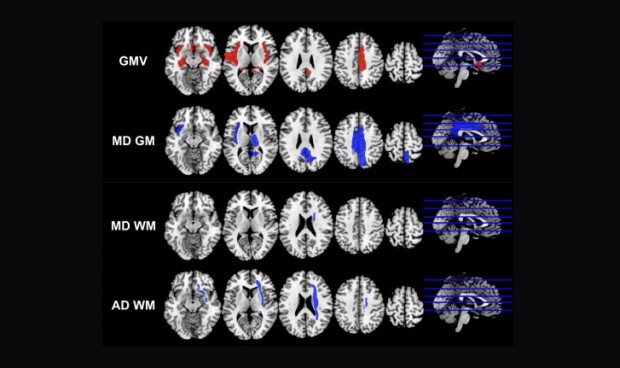

Imagen de las resonancias.

A tal forma, se resolvía que en los pacientes con Covid-19 recuperados “tenían más probabilidades de tener cortezas olfativas agrandadas, hipocampo, ínsula, circunvolución de Heschl, opérculo rolándico y circunvolución del cíngulo, y una disminución general de la difusividad media (DM), la difusividad axial (DA), la difusividad radial (RD) acompañada de un aumento de la anisotropía fraccional (FA) en la sustancia blanca, especialmente la EA en la radiación coronaria derecha (CR), la cápsula externa (CE) y el fascículo frontal-occipital superior (SFF), y DM en SFF.

Del mismo modo, se encontró que el volumen global de materia gris (GMV), GMV en opérculo rolándico izquierdo, cíngulo derecho, hipocampo bilateral, circunvolución de Heschl izquierda, y Global MD of WM se correlacionan con la pérdida de memoria. "Los GMV en la circunvolución del cíngulo derecho y el hipocampo izquierdo se relacionaron con la pérdida del olfato. La puntuación MD-GM, GMV global y GMV en la circunvolución cingulada derecha se correlacionaron con el nivel de lactato deshidrogenasa (LDH)”, informan también los firmantes del estudio retrospectivo.

Es importante reseñar que, según dicho informe, durante la infección por SARS-CoV-2, el 68,33 por ciento de los pacientes del estudio tuvieron síntomas neurológicos y más del 50 por ciento de los pacientes recuperados todavía tenían síntomas 3 meses después. “Encontramos que el GMV en el hipocampo (una parte clave en la organización de la memoria) y las circunvoluciones del cíngulo (una parte importante del sistema límbico) se relacionaron negativamente con la pérdida del olfato durante la infección y la pérdida de la memoria 3 meses después, lo que podría apoyar nuestra hipótesis de neurogénesis en estas regiones mencionadas anteriormente”.